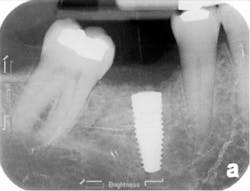

The patient was seen four months later for Stage II uncovering of her implant using a tissue punch and was sent to her restorative dentist for final impressions two weeks after that. Three months after the initial surgery, the patient returned with her final restoration in place for a soft-tissue exam and radiograph. Six months after surgery, she returned for a postdelivery radiograph, shown here. (I see every implant patient three months after seating the final restoration to check for residual cement, ensure that the restorative apparatus is fully seated, and check the soft- and hard-tissue response to the new restoration. This is an extremely important—and often overlooked visit—where problems are often noted that can cause significant damage to the bone and gingiva if early intervention is not initiated.) The bone levels were well-maintained around the implant platform, and the soft-tissue health was excellent. The patient reported a high degree of satisfaction with her new implant restoration.